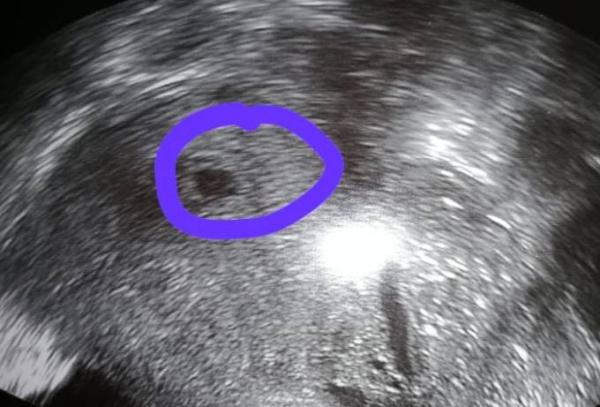

Hallo lieber Juli-Bus! Ich war heute bei meinem ersten Frauenarzttermin. Den Frauenarzt habe ich gewechselt und bin jetzt bei einem Mann. Aber das war echt prima. Sehr sympathisch. Und meine Tochter und meinen Mann durfte ich auch mitbringen. Nicht wie bei den anderen Ärzten, bei denen die Partner nicht mehr mit dürfen. Auf jeden Fall durften wir heute unsere kleine Blase sehen (5+1 oder 5+2). Jetzt noch einmal gut zweieinhalb Wochen warten und dann sehen wir hoffentlich auch den Krümel mit . Aber da bin ich guter Hoffnung. Er sagte, er solle noch warten, es auf Arbeit zu sagen, mindestens den nächsten Termin noch abwarten. Das mache ich dann auch. Wäre ich nicht im Urlaub, hätte er mich auch so lange krank geschrieben. Gegen Übelkeit hat er mir auch ein Rezept ausgestellt. Es heißt Cariban. Falls es wieder so schlimm wird. Soll noch recht neu sein, aber Frauen berichten wohl von einer guten Wirkung.

Bild zu Fruchtblase gesichtet - Forum für Juli - Mamis